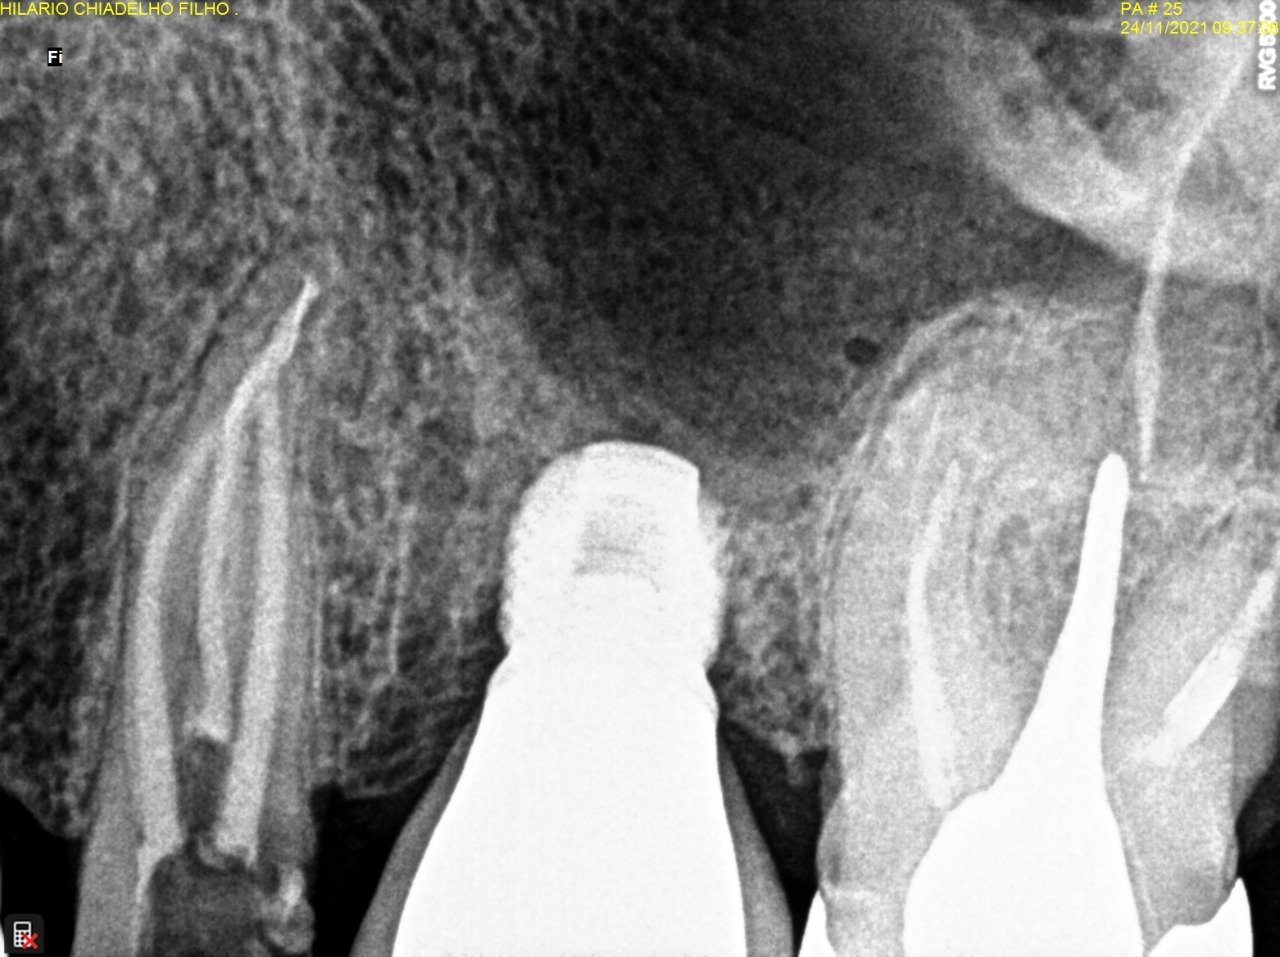

Remoção de broca gates fraturada dentro do canal

De acordo com a imagem abaixo foi feita a remoção de um fragmento fraturado dentro do canal utilizando pontas especificas de ultrassom.